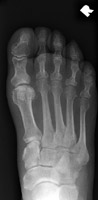

- Click on the image for a larger versionBAP radiograph of the foot demonstrates a fracture of the fourth proximal phalanx.